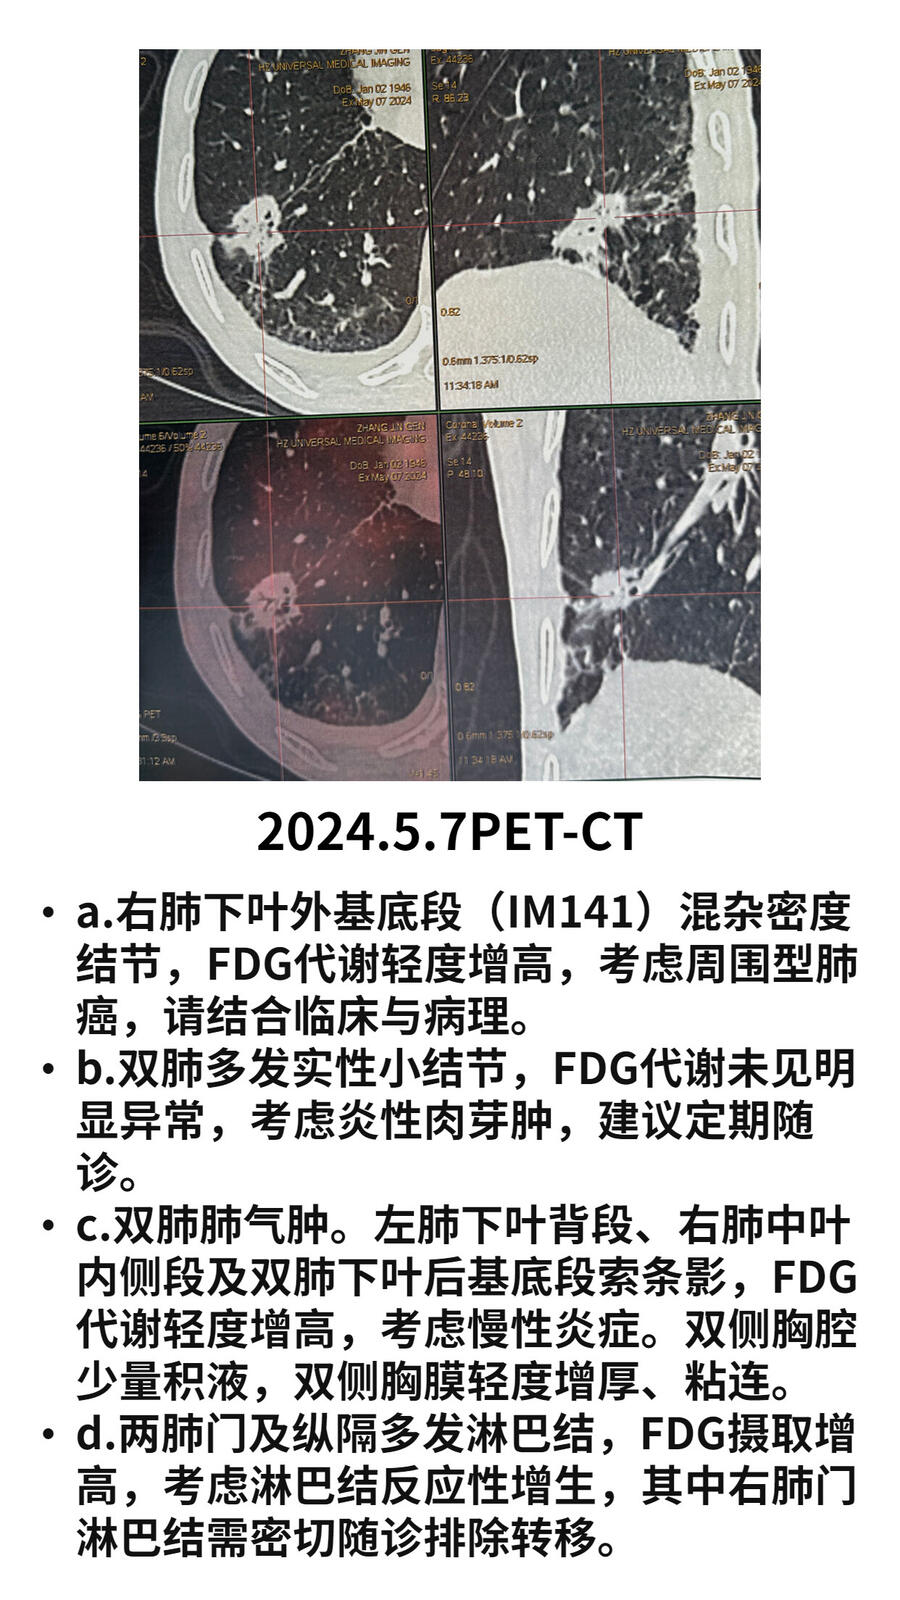

进一步PET检查显示右肺占位代谢增高,但是肺占位中空洞表现。建议患者进一步抗炎治疗后复查。